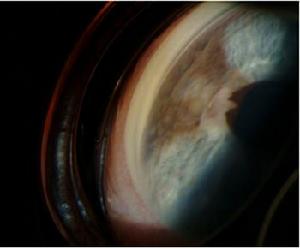

原發性急性閉角型青光眼病理圖1.血管改變 急性高眼壓可造成眼內小血管阻塞,常見於虹膜和睫狀體一個節段的虹膜、睫狀體血管阻塞,使該區域虹膜睫狀體缺血萎縮、脫色素、睫狀突玻璃樣變等。虹膜萎縮可延至周邊房角,每次急性發作都可有新的萎縮區出現。該部位的括約肌或同時伴有開大肌功能喪失,嚴重者瞳孔永久性散大固定呈橢圓形,縮瞳劑和散瞳劑均無作用。嚴重虹膜萎縮時色素脫失、基質變薄甚至前後房交通房水可以由該處從後房直接進入前房。一處或兩處的虹膜萎縮如同虹膜切除術,可以緩解瞳孔阻滯。另外,虹膜萎縮區所對應的房角相應加寬,不再有虹膜擁堵可防止房角進一步關閉。因此,這一改變的直接病理意義是防止青光眼再發作。當虹膜萎縮較輕,特別是僅有過小發作而處於緩解狀態的眼輕度的瞳孔變形瞳孔緣變薄亦可提示該區域的虹膜已有萎縮應仔細檢查以免漏診。